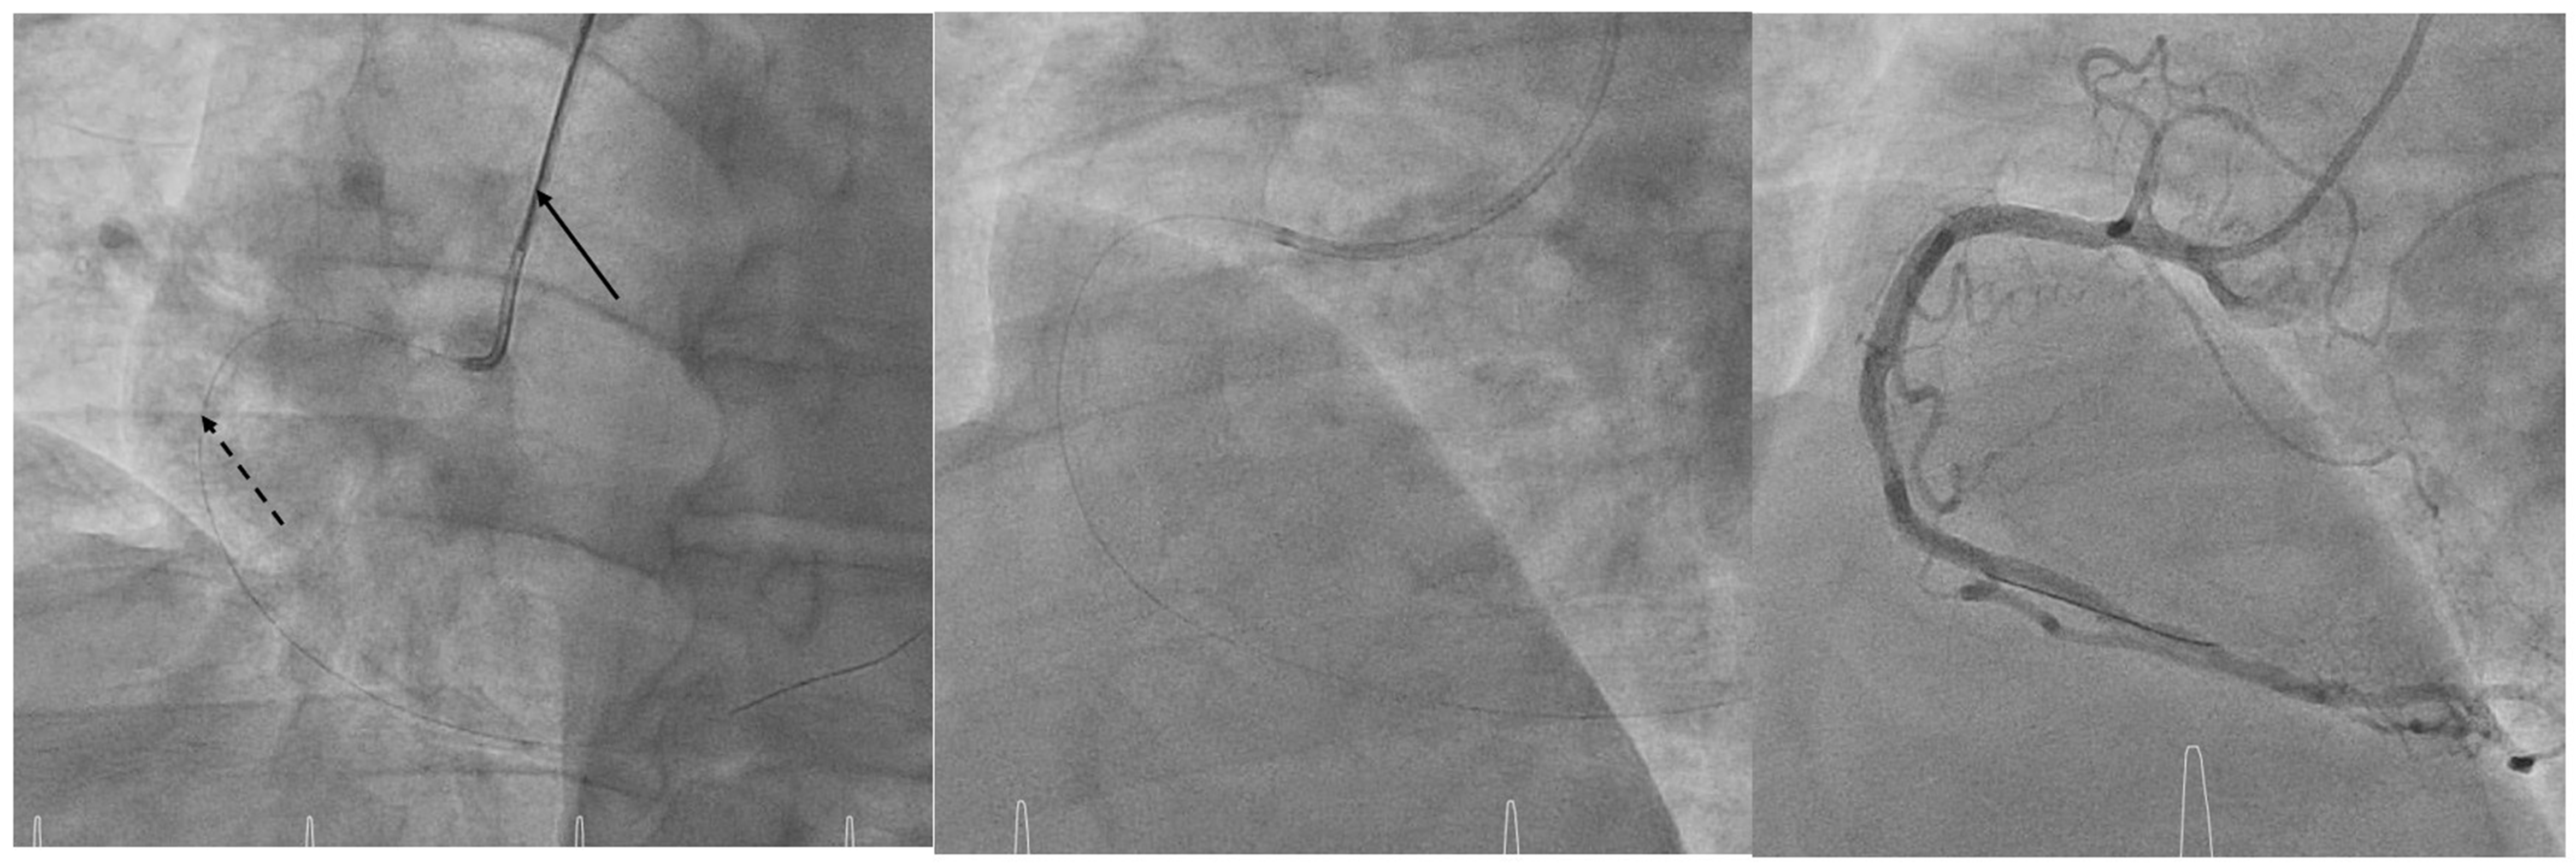

Following left coronary injections, the stiff wire is advanced so that its rigid segment extends just beyond the first curve of the catheter, straightening it into a shape mimicking a JR4 or multipurpose configuration (Figure 1). The wire is left in place during RCA injections to maintain support and coaxial alignment (Figure 2). Notably, the residual lumen of a 5F guiding catheter with a 0.032-inch wire in place (~1.06 mm²) exceeds that of a standard 5F diagnostic catheter (~0.95 mm²), ensuring safe and effective contrast delivery (Figure 3).

FAST-CATH offers several advantages: it allows complete coronary angiography with a single catheter; avoids catheter exchange; reduces procedure time, radial trauma, and spasm risk; and enables immediate transition to fractional flow reserve or ad hoc percutaneous coronary intervention (PCI). If PCI is required, a 0.014-inch wire can be advanced alongside the 0.032-inch wire, which is then withdrawn (Figure 4).